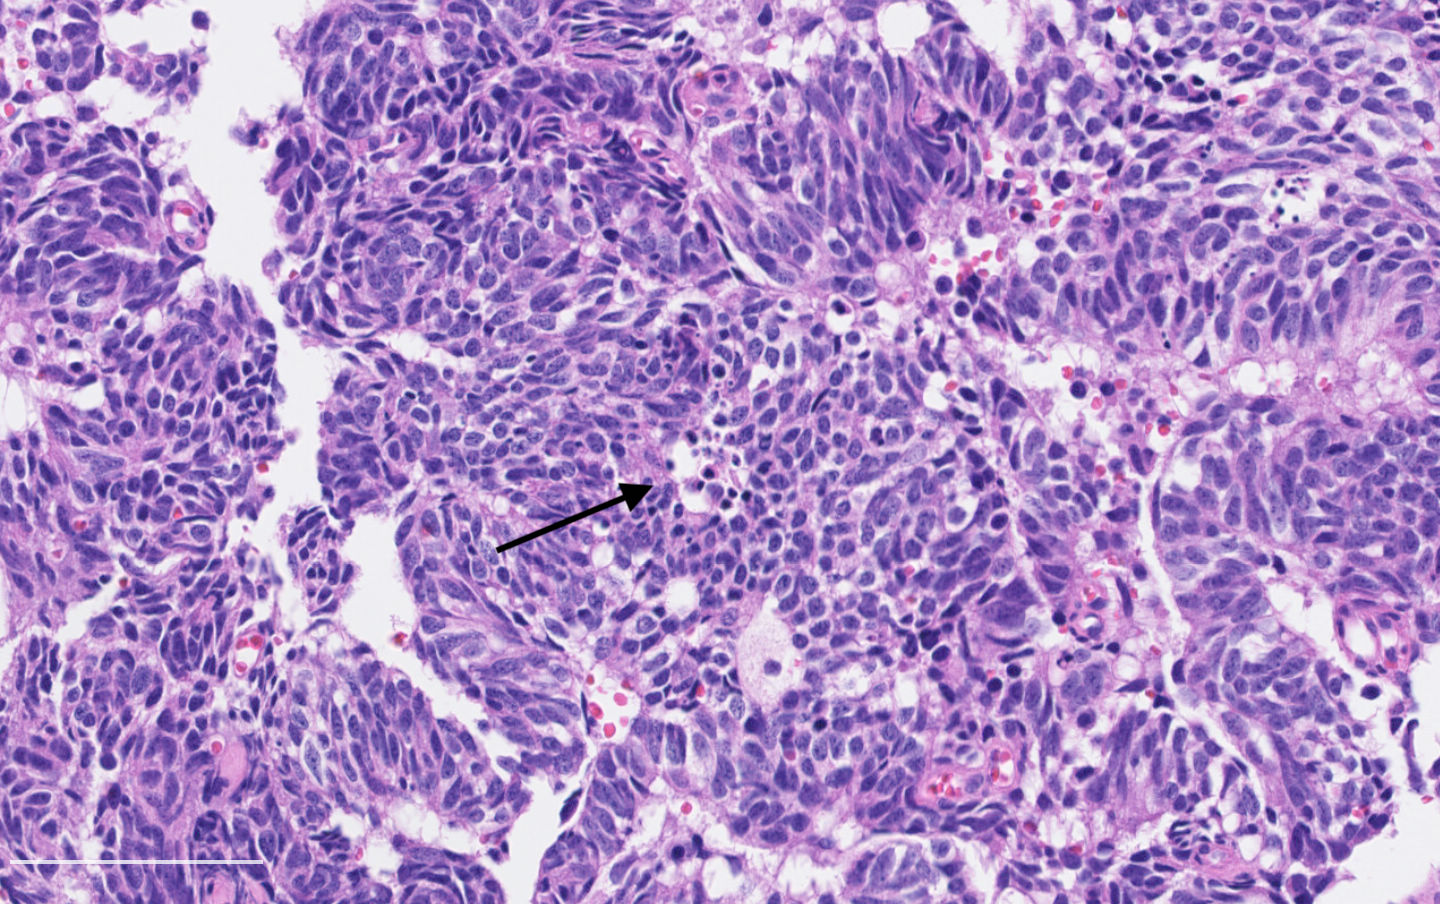

- Diagnostic criteria:

- Neuroendocrine morphology with 2 - 10 mitoses per 2 mm² or presence of necrosis

- Mitotic rate should be counted in the area with the highest proliferation rate (hot spot)

- Neuroendocrine morphology with 2 - 10 mitoses per 2 mm² or presence of necrosis

- Neuroendocrine histologic patterns similar to typical carcinoids: organoid, trabecular, rosette formation, papillary, pseudoglandular, follicular

- Tumor cells are as typical carcinoid: uniform with a polygonal shape, round to oval nuclei with salt and pepper chromatin and inconspicuous nucleoli, along with moderate to abundant eosinophilic cytoplasm

- Greater pleomorphism than for typical carcinoid is common (Arch Pathol Lab Med 2010;134:1628)

- Spindle cells and clear cell features can be seen

- Stroma is fine and highly vascularized; hyalinization, cartilage or bone formation are possible

Contributed by Philippe Joubert, M.D., Ph.D.